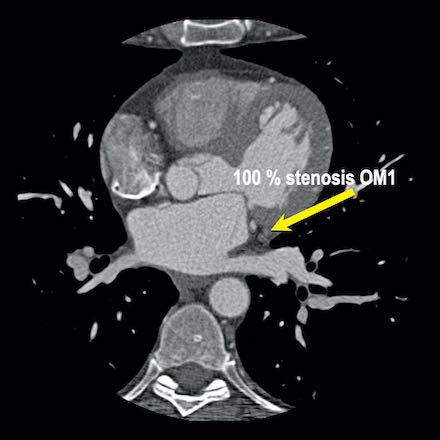

case 2 – CAD-RADS 5/P2/S

First, scroll through the CTA images.

How would you describe the findings on the coronary CTA?

The findings are:

- Stent in the mid

LAD with low-attenuation within the stent suggestive of minimal in-stent

restenosis (<25%). Non-calcified plaque distal to the stent

causing mild stenosis (25-49%). Notice bridging on a short segment in

the distal LAD. - Non-calcified

plaque in the LCX causing mild stenosis (25-49%). - Occlusion of the

proximal OM1 branch with distal filling. - Calcified and

non-calcified plaques in the proximal RCA causing mild (25-49%) stenosis. - Total plaque burden

is moderate based on SIS (four segments including proximal RCA, mid LAD, prox

LCX and OM1).

Due to the occlusion of OM1 branch and presence of the stent, this case

reads as CAD-RADS 5/P2/S, which means that this patient needs further

diagnostic workup.